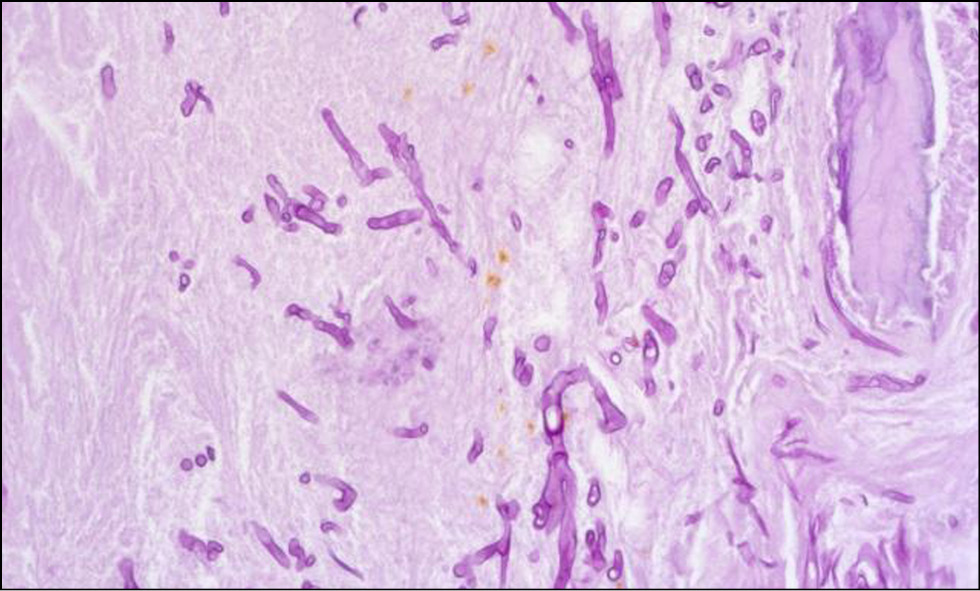

Для оценки патологического процесса исследован материал, взятый из некротизированных участков. Образец ткани фиксирован в 10%-м растворе забуференного формалина. Костные фрагменты после фиксации декальцинировались 1 сут в электролитном декальцинирующем растворе соляной и муравьиной кислот. Процессинг материала (обезвоживание, обезжиривание и пропитка парафином) осуществлен с применением автоматического вакуумного гистопроцессора Leica ASP200, образец залит в парафиновый блок с помощью станции заливки Thermo Scientific HistoStar, на ротационном микротоме Leica RM2265 изготовлены срезы с парафинового блока толщиной 4 мкм, окрашены гематоксилином-эозином по стандартной методике, а также ШИК-реакцией (PAS) и импрегнацией серебром по Грокотт для обнаружения мицелия грибов. Оценка окрашенных микропрепаратов проводилась методом световой микроскопии с использованием микроскопа Zeiss AxioLab.A1.

В полученных срезах визуализировались фрагменты (рис. 13) некротизированной слизистой оболочки (безъядерный эозинофильный субстрат с очертаниями предсуществующих структур) с наложениями детрита, распадающихся нейтрофилов, базофильных колоний микроорганизмов, раздробленных широких лентовидных гифов грибов, местами ветвящихся под прямым углом (рис. 14), и фрагменты костной ткани с широкими костно-мозговыми полостями, заполненными клеточно-тканевым детритом, распадающимися нейтрофилами, базофильными колониями микроорганизмов, раздробленными широкими лентовидными гифами грибов аналогичного вида (рис. 15), дающих положительную реакцию при окраске по PAS (рис. 16) и Грокотт (рис. 17).

Рис. 16. Окраска — ШИК-реакция (PAS). 200×. В центральной части — мицелий гриба, дающий положительную реакцию

Рис. 17. Окраска — импрегнация серебром по Грокотт. 200×. В центральной части — мицелий гриба, дающий положительную реакцию